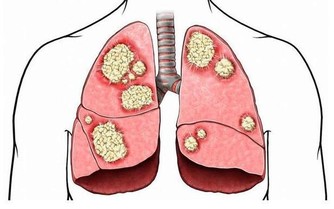

人到了一定歲數,或者終年食用高脂肪飲食,血管內膜增厚,就會構成“斑塊”,易致使動脈狹窄,特別是血管分支入口,血流艱難,易發作阻塞。

你的動脈阻塞缺血嗎?